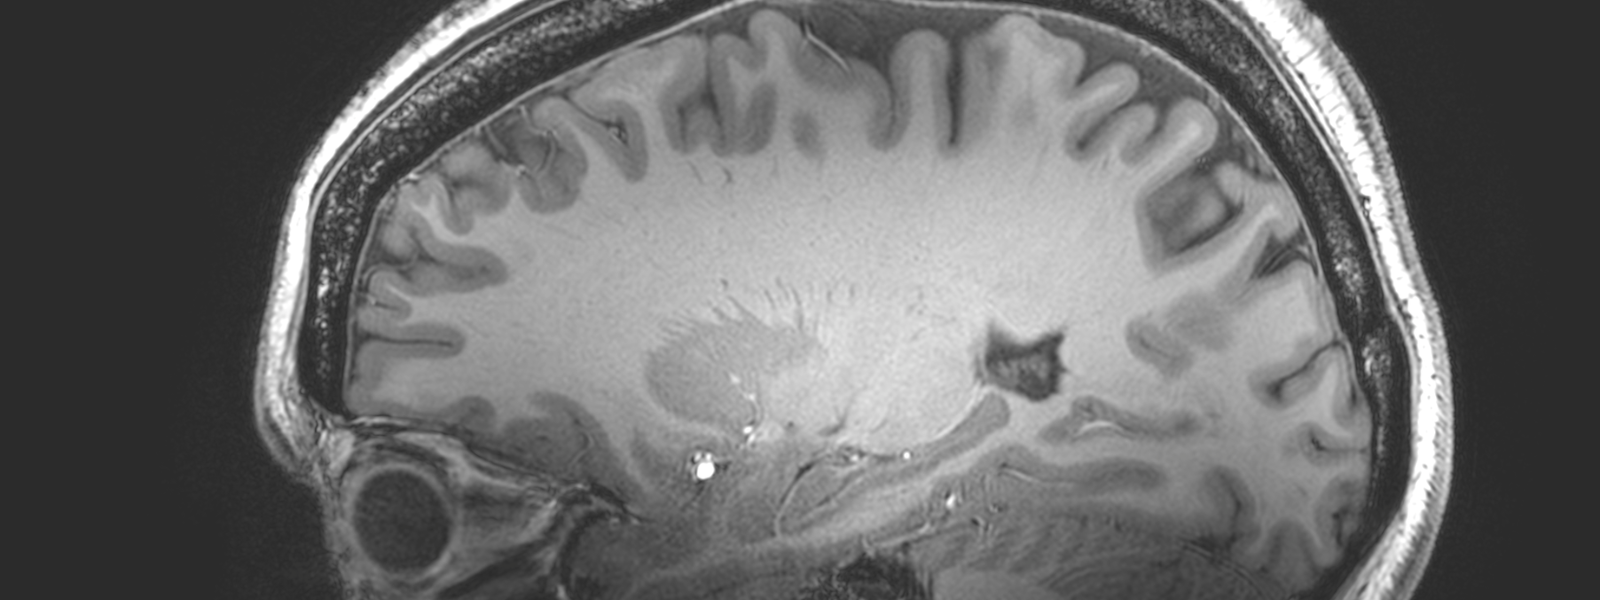

The University of Nottingham has been awarded £29.1 million to establish the UK’s most powerful Magnetic Resonance Imaging (MRI) scanner as a national facility, subject to business case approval. This scanner will give researchers and doctors unprecedented insights into brain function and the mechanisms of human disease.

The University of Nottingham will work with teams across the UK to establish the 11.7T Tesla MRI scanner as a national facility that will underpin the UK’s goal of retaining its position as a world leader in ultra-high field for brain imaging and spectroscopy. The new ultra-high field scanner will be sited in the Sir Peter Mansfield Imaging Centre at the University of Nottingham. Nobel Prize winner Sir Peter Mansfield developed MRI in Nottingham in the early 1970s, revolutionising healthcare across the world.

The capabilities of this new scanner will underpin a broad range of clinical and neuroscience-focused research programmes in the UK. It will be more than 1000 times more powerful than the first scanners developed by the late Sir Peter and will help transform understanding of neurodegenerative diseases such as Alzheimer’s, Parkinson’s and Huntington’s and neurodevelopmental disorders including autism and schizophrenia.

Ultra-high field (11.7T) MRI offers huge benefits in terms of improved sensitivity which will enable higher spatial resolution imaging, faster imaging, and greater sensitivity to physiological changes. The scanner will also provide a step change in the capabilities of magnetic resonance spectroscopy (MRS) to provide information about the biochemistry of the human body.